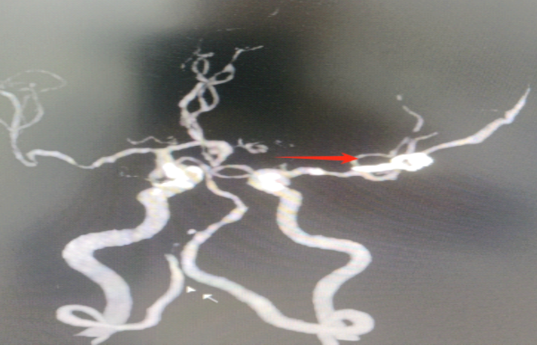

▲CTA:箭头示动脉瘤夹,瘤体夹闭完全

患者病情危重,诊断考虑:右侧大脑中动脉瘤破裂并脑内血肿,占位效应明显,且有继续出血脑疝形成可能。我科手术团队经充分讨论后认为需急诊开颅脑动脉瘤夹闭术,患者家属同意后予急诊绿色通道送手术室手术治疗。术程顺利,术后患者苏醒,在院康复治疗中。